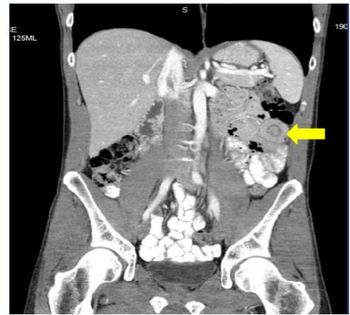

Intussusception in the Adult Patient: Rare, Ominous BySean Sims, PA-C,Jennifer Bell, PA-CJanuary 11th 2016Most adult intussusceptions are caused by structural lesions, lead points for many of which are malignant neoplasms.